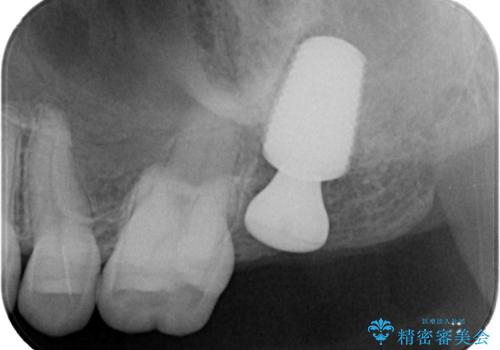

根尖病巣も大きかったため先に抜歯を行い、1ヶ月後にインプラントを埋入しました。

インプラントの埋入から被せものの装着まで2ヶ月で終えることができました。治療期間も短く、しっかり咬めるため大変喜んでいただきました。